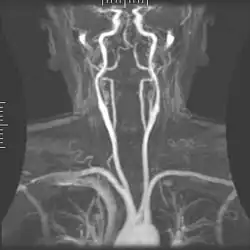

Kontrastverstärkte MRA

Durch die Injektion von T1-verkürzendem (meist gadoliniumbasiertem) Kontrastmittel wird das Blut auf T1-gewichteten MRT-Aufnahmen signalreich dargestellt. MRT-Aufnahmen während des Durchflusses des Kontrastmittels durch ein Organ oder eine anatomische Region können daher eingesetzt werden, um die Blutgefäße darzustellen. Die kontrastverstärkte MRA (CE-MRA von engl. contrast-enhanced MRA, gelegentlich auch KM-MRA von Kontrastmittel-MRA) basiert auf schnellen in der Regel dreidimensionalen Gradientenecho-Techniken (FLASH).

Im Vergleich zur Time-of-Flight- oder Phasenkontrast-MRA kann die Aufnahmedauer bei der kontrastverstärkten MRA deutlich verkürzt werden, so dass Aufnahmen bei angehaltenem Atem ebenso möglich werden wie dynamische MRA-Aufnahmen, die den Blutfluss zeitaufgelöst darstellen können (mit Zeitauflösungen bis herab zu 1 Sekunde je 3D-Datensatz).